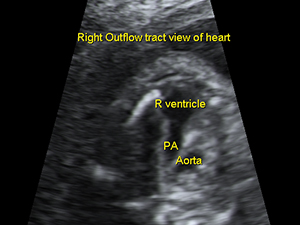

胎兒心臟肺動脈外流道平面圖